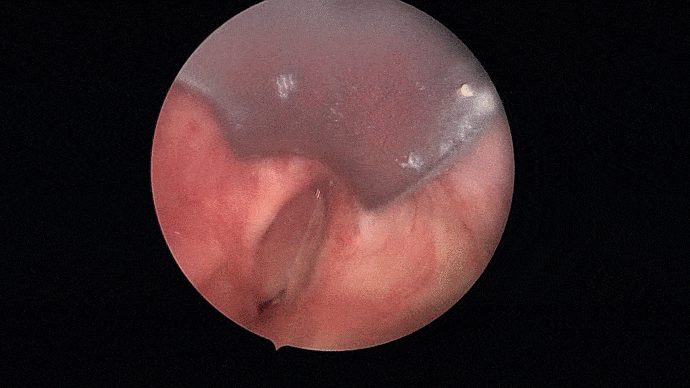

Les troubles de la voix sont analysés puis les cordes vocales sont examinées grâce à système optique afin de proposer une prise en charge adaptée.